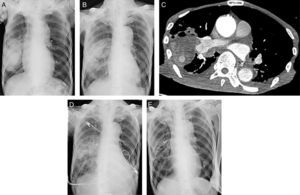

Un varón exfumador de 79 años acudió a nuestro hospital por presentar tos húmeda y pérdida de peso de un mes de evolución. Un año antes se le había diagnosticado infarto cerebral y fibrilación auricular crónica y recibía 15mg de rivaroxabán una vez al día. La radiografía de tórax mostró una masa de 12,8×7,0cm en el área inferior del pulmón derecho (fig. 1A). En la fibrobroncoscopia se observaron esputos purulentos en gran volumen, que no obstruían la vía aérea, compatibles con un absceso pulmonar. El cultivo del esputo resultó negativo, por lo que se inició tratamiento antibiótico empírico con tazobactam/piperacilina. En la radiografía de tórax realizada tras 4 días de hospitalización se observó una ligera mejoría del absceso (fig. 1B), pero una semana más tarde, el paciente presentó hemoptisis. Se practicó una tomografía axial computarizada (TAC) que reveló un nódulo que se intensificaba con el contraste, en el interior del absceso (fig. 1C), compatible con un PAP. Al día siguiente, debido a la persistencia de la hemoptisis y a la insuficiencia respiratoria progresiva se practicó una embolización de la rama A5 derecha de la arteria pulmonar con 2 espirales extraíbles Interlock® (Boston Scientific Corp), 4 espirales de embolización Hilal® y una espiral de embolización Tornado® (Cook Medical). La TAC torácica con contraste practicada el segundo día después de la embolización mostró la desaparición del nódulo intensificado y en la radiografía de tórax del tercer día se observó una marcada disminución del tamaño del absceso (fig. 1D). Un mes más tarde, la radiografía de tórax mostró la resolución casi completa del absceso (fig. 1E). Sin embargo, el paciente falleció repentinamente 39 días después de su ingreso. La causa de la muerte no se pudo esclarecer porque la familia rechazó la necropsia.